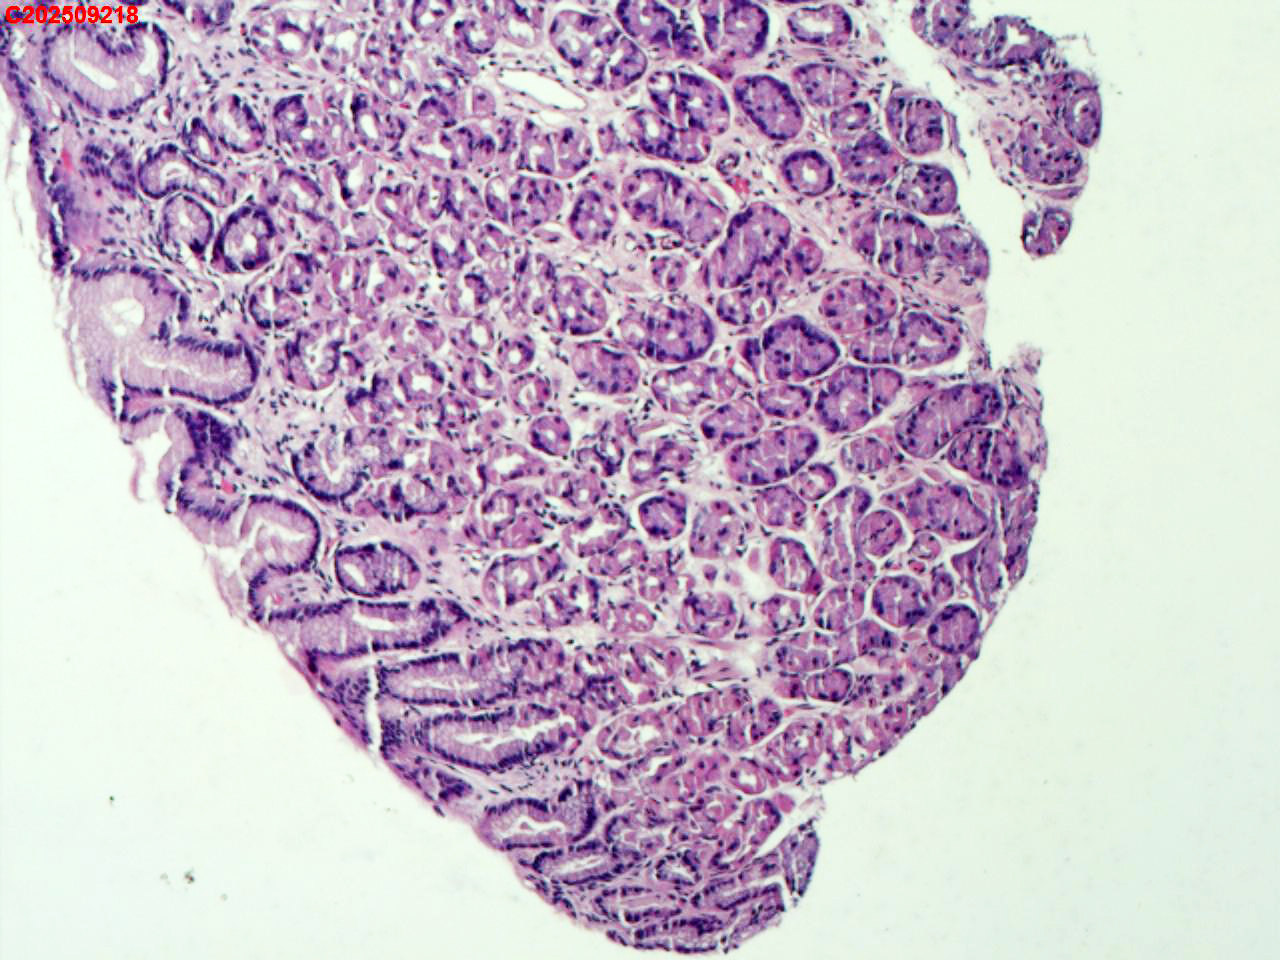

胃体粘膜

胃息肉

体检

胃体可见一枚直径2mm息肉。

胃底腺息肉

小凹增生。

增生性息肉